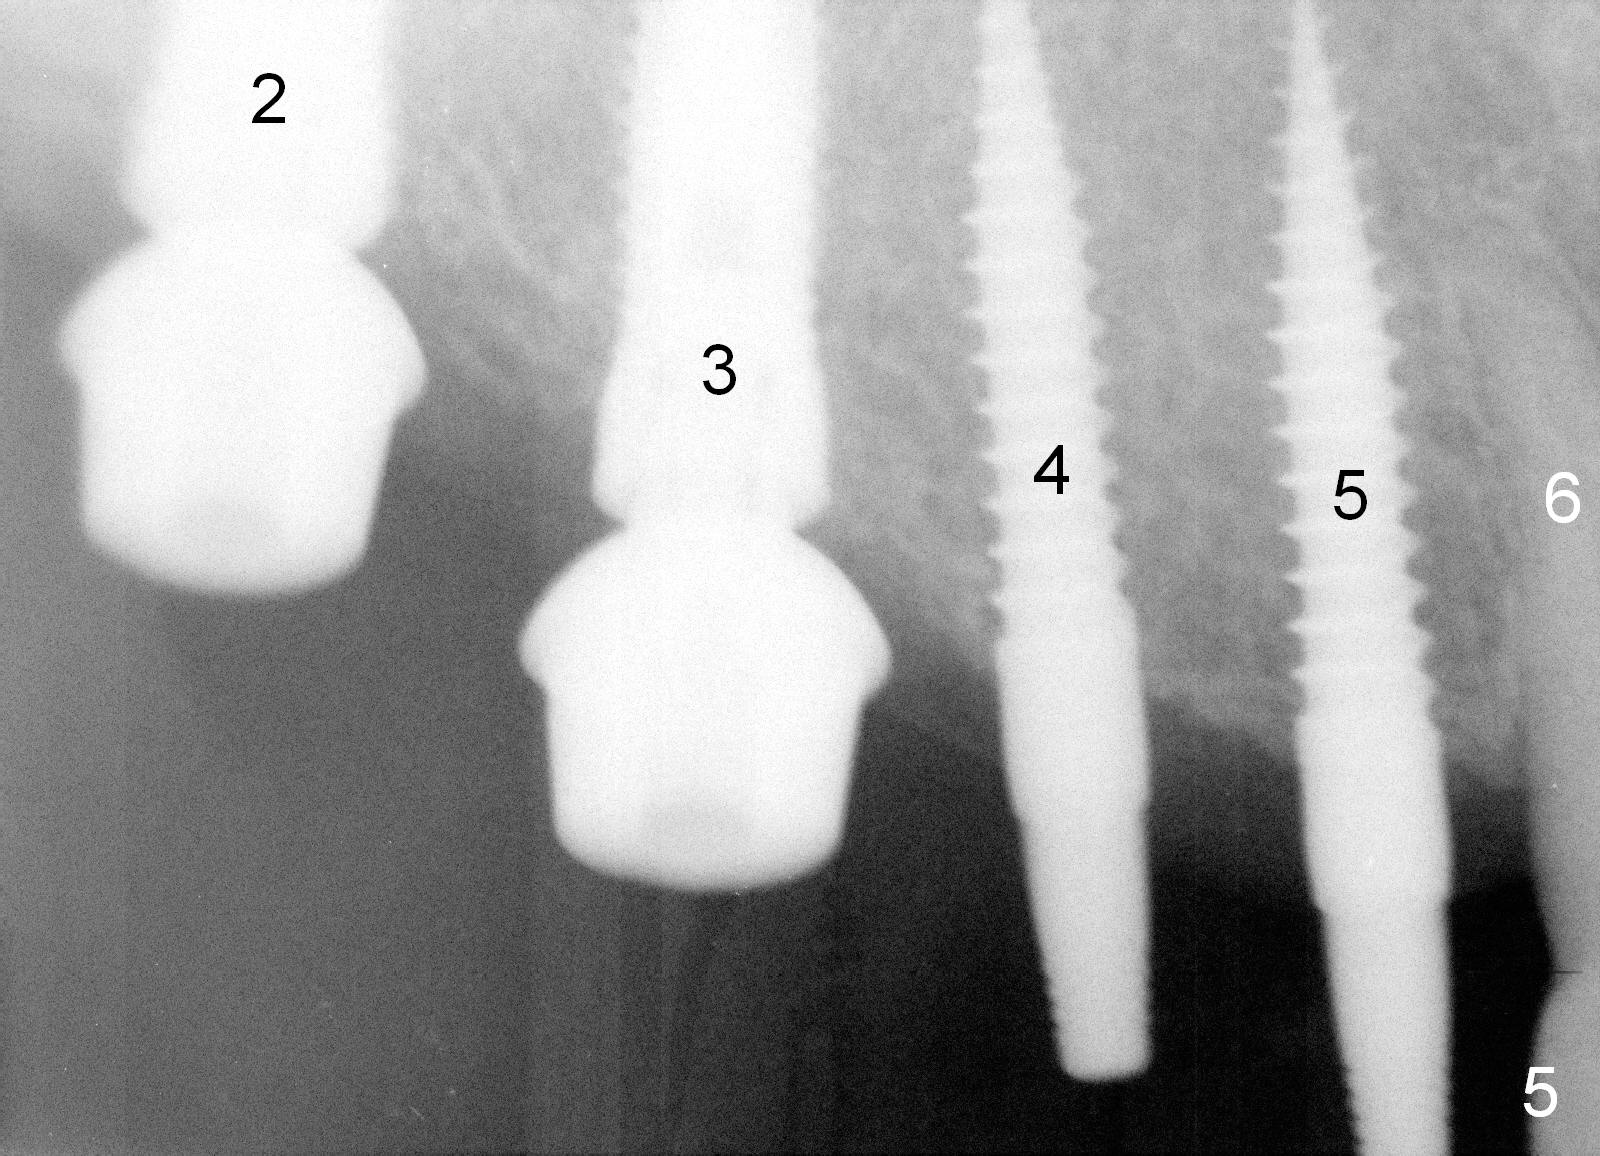

Osteotomy in the upper posteriors starts through a surgical stent for 12 mm. After incision, each osteotomy is examined, adjusted and extended 2 mm shy of intended (Fig.1,2). It appears that the trajectories at #4,5 are off (Fig.2). After re-adjustment, the trajectories are acceptable (Fig.3 (red dashed line; part of the root of the tooth #6)). Four implants are placed basically in accordance with the plan: 5.9x10 mm at #2, 5x14 at 3, and 3x14 mm 1-piece at 4 and 5 (Fig.4,5). Fig.6 shows the narrow ridge at #4 and 5 after implant placement. Although abutments are placed at #2 and 3, an immediate provisional bridge cannot be fabricated because of lack of enough clearance (supraeruption of the opposing dentition).

Drilling through the surgical stent helps establish the initial osteotomy, especially the mesiodistal position.